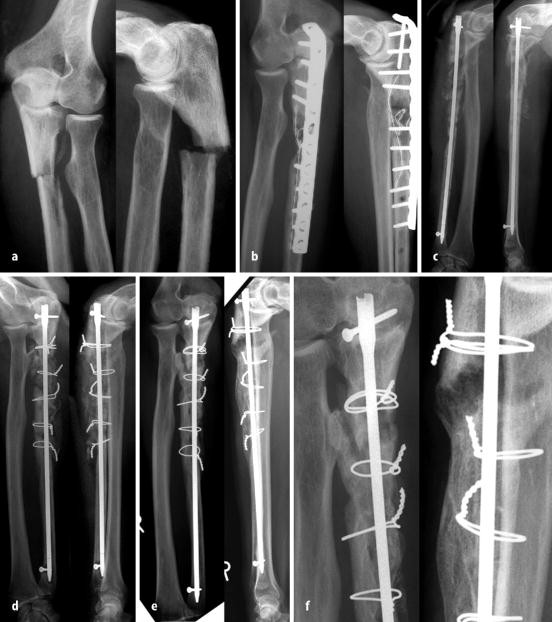

Effiziente Diagnostik Pathologischer Frakturen Sciencedirect

Figure 3 Die Pathologische Fraktur Aus Sicht Des Orthopaden Und Unfallchirurgen Springerlink